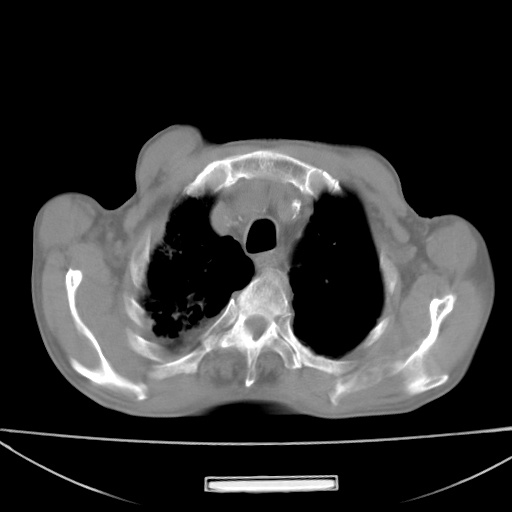

标题: CT13796:请会诊右上费病变!

患者男80岁,反复咳嗽多年,咳喘伴咯血1月

右上肺周围型肺癌伴肺门淋巴结转移.右上肺继发型肺结核.

右肺尖周围型肺癌伴肺门淋巴结肿大

右肺尖结核

右上肺周围型肺癌伴肺门淋巴结转移。支持!另:右肺继发性肺结核!

右上肺周围型肺癌伴肺门、纵膈淋巴结转移

考虑为:右肺上叶肺癌伴阻塞性肺炎、右肺门及纵膈淋巴结转移。